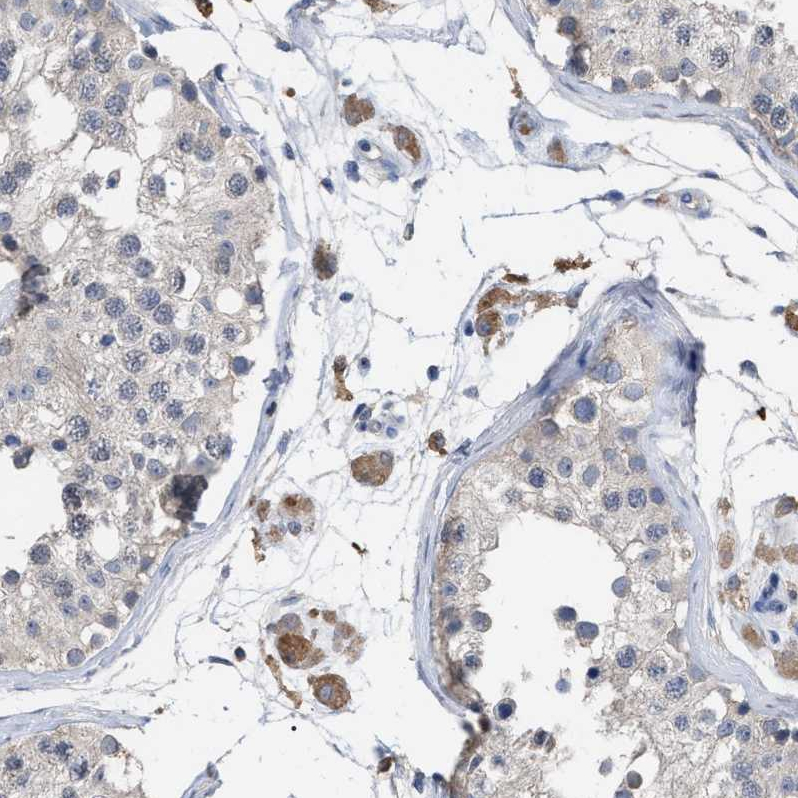

Immunohistochemical staining of human pancreatic cancer shows moderate membranous positivity in tumor cells.